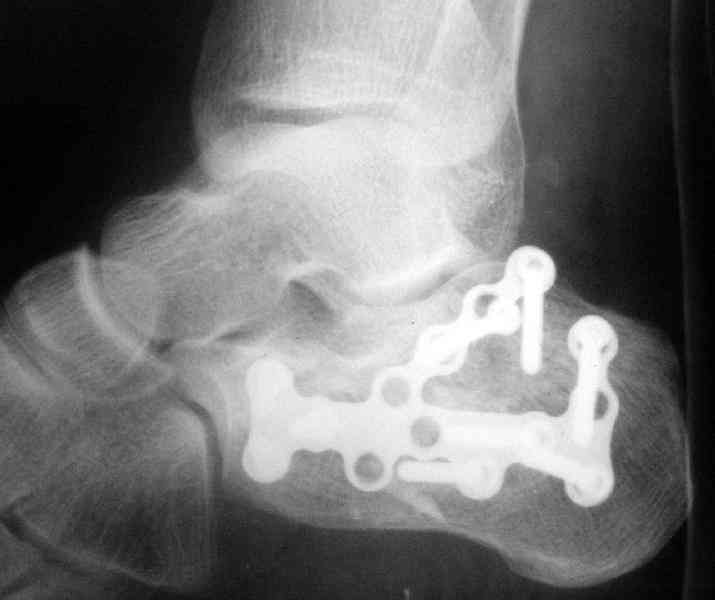

Re: Перелом пяточной кости

послал А.П.Ким 09 Октябрь 2007, 09:41

Открытый и закрытый способы лечения.